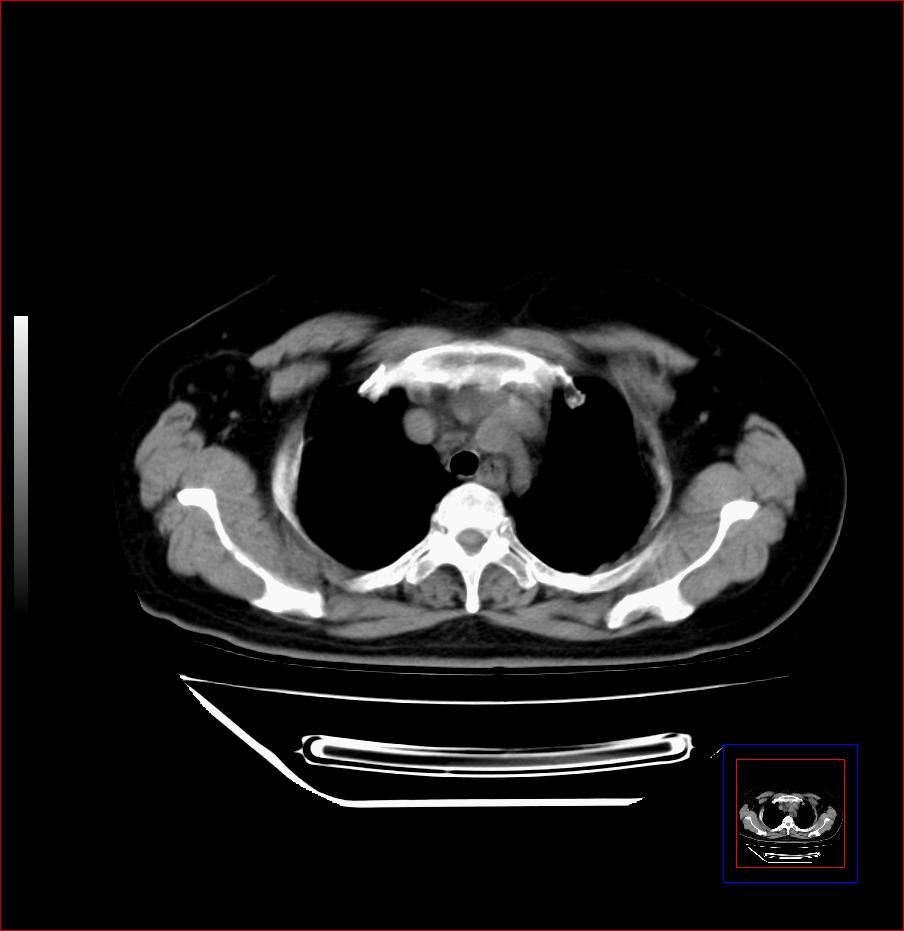

标题: CT25445:上段食管正常吗?

女,56岁,胸部体检,无不适。感觉食管壁略厚,最后约6mm.谢谢大家讨论,主要是自己亲人,疑神疑鬼的。主动脉弓旁淋巴结还有点肿大。